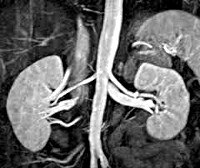

Гормональную активность опухоли надпочечников можно оценить, используя селективную надпочечниковую флебографию – рентгенконтрастную катетеризацию надпочечниковых вен с последующим забором крови и определением в ней уровня гормонов. Исследование противопоказано при феохромоцитоме, т. Может спровоцировать развитие криза. Размеры и локализацию опухоли надпочечников, наличие отдаленных метастазов оценивают по результатам УЗИ надпочечников, КТ или МРТ. Эти диагностические методы позволяют выявить опухоли- инциденталомы диаметром от 0,5 до 6 тд.